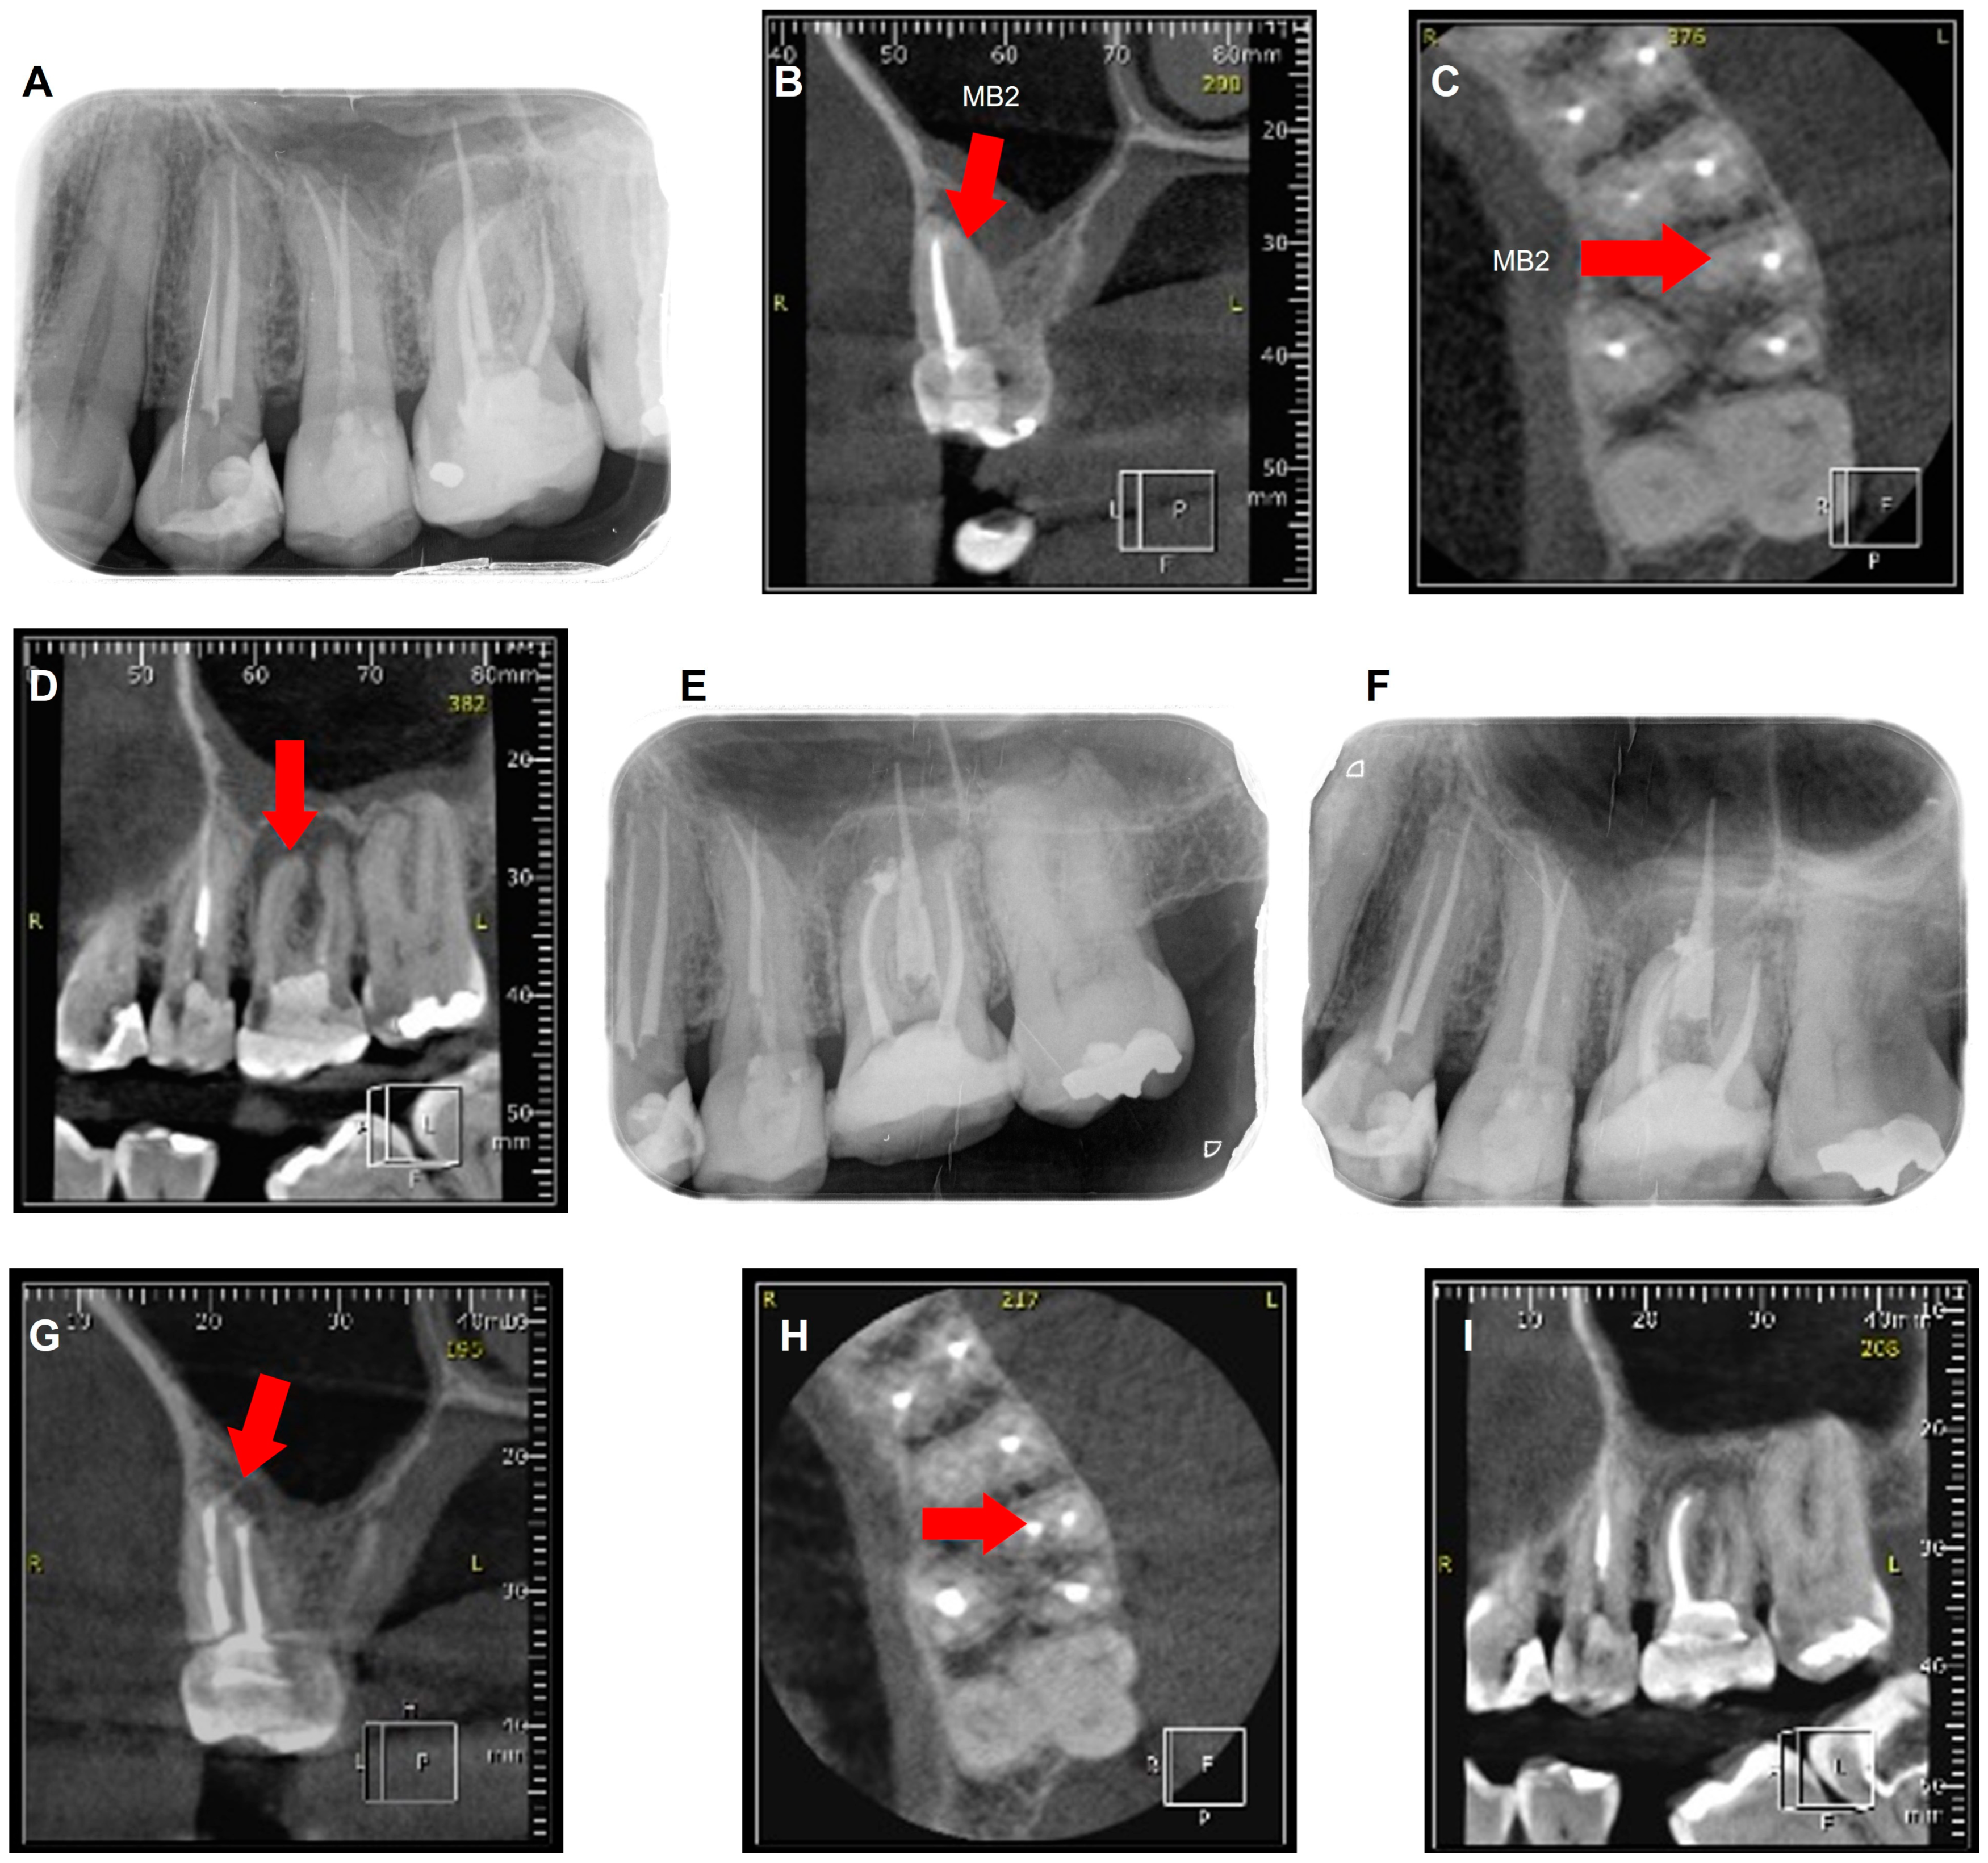

2.1. Case 1